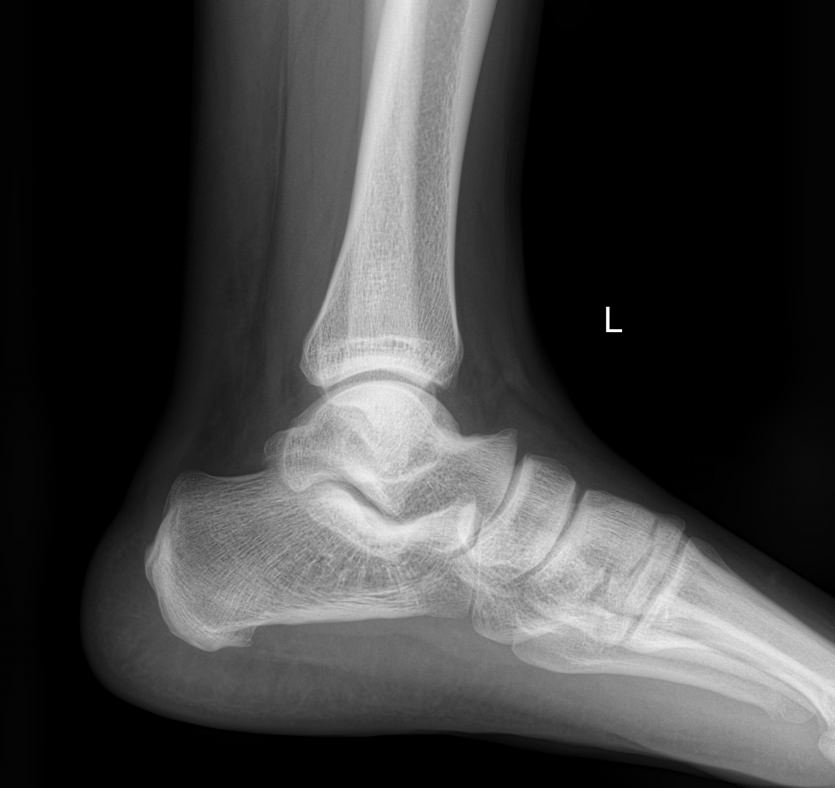

Голеностопные суставы отличаются сложным строением, в позволяющим стопе вращаться, сгибаться и разгибаться почти на 90о. Благодаря этому тело свободно перемещается в пространстве, меняет свое положение, поднимает собственный вес и дополнительный груз. Травмы голеностопных суставов встречаются также часто, как и хронические заболевания.

В качестве скринингового, а зачастую и единственного метода диагностики голеностопных суставов обычно используют рентген. Его вполне достаточно для визуализации внутреннего строения сустава и патологических изменений в нем. А цифровая нагрузка цифрового оборудования последнего поколения  несет минимум излучения и позволяет безопасно делать несколько снимков подряд.

Обследование обоих суставов с помощью рентгена помогает подтвердить диагноз, сравнить проявления на разных ногах, установить стадию заболевания, выбрать тактику лечения и определить его эффективность при следующих патологиях:

• Переломы и вывихи;

• Врожденные аномалии;

• Онкология;

• Дегенеративно-дистрофические заболевания.

• Изменения, произошедшие в костной ткани элементов суставов ― разрежение, некроз, озлокачествление, склерозирование;

• Нарушение четкости контуров костных образований;

• Перелом, его местоположение, смещение отломков;

• Состояние суставных щелей ― сужение, расширение, скопление жидкости, обызвествление капсулы;

• Конгруэнтность суставных поверхностей или вывих;

• Состояние мягких тканей ― отеки, инородные тела.